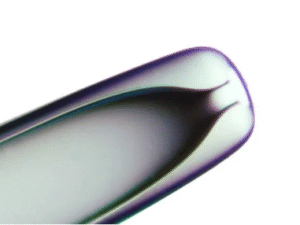

Sunlight Medical Holding Pipette SHP-130B-xx

Holding Pipettes

-Holding pipettes are used to hold an oocyte or embryo in position during ICSI and other micro-manipulation procedures.

-There are 3 series with various dimensions for selection.Holding Pipettes